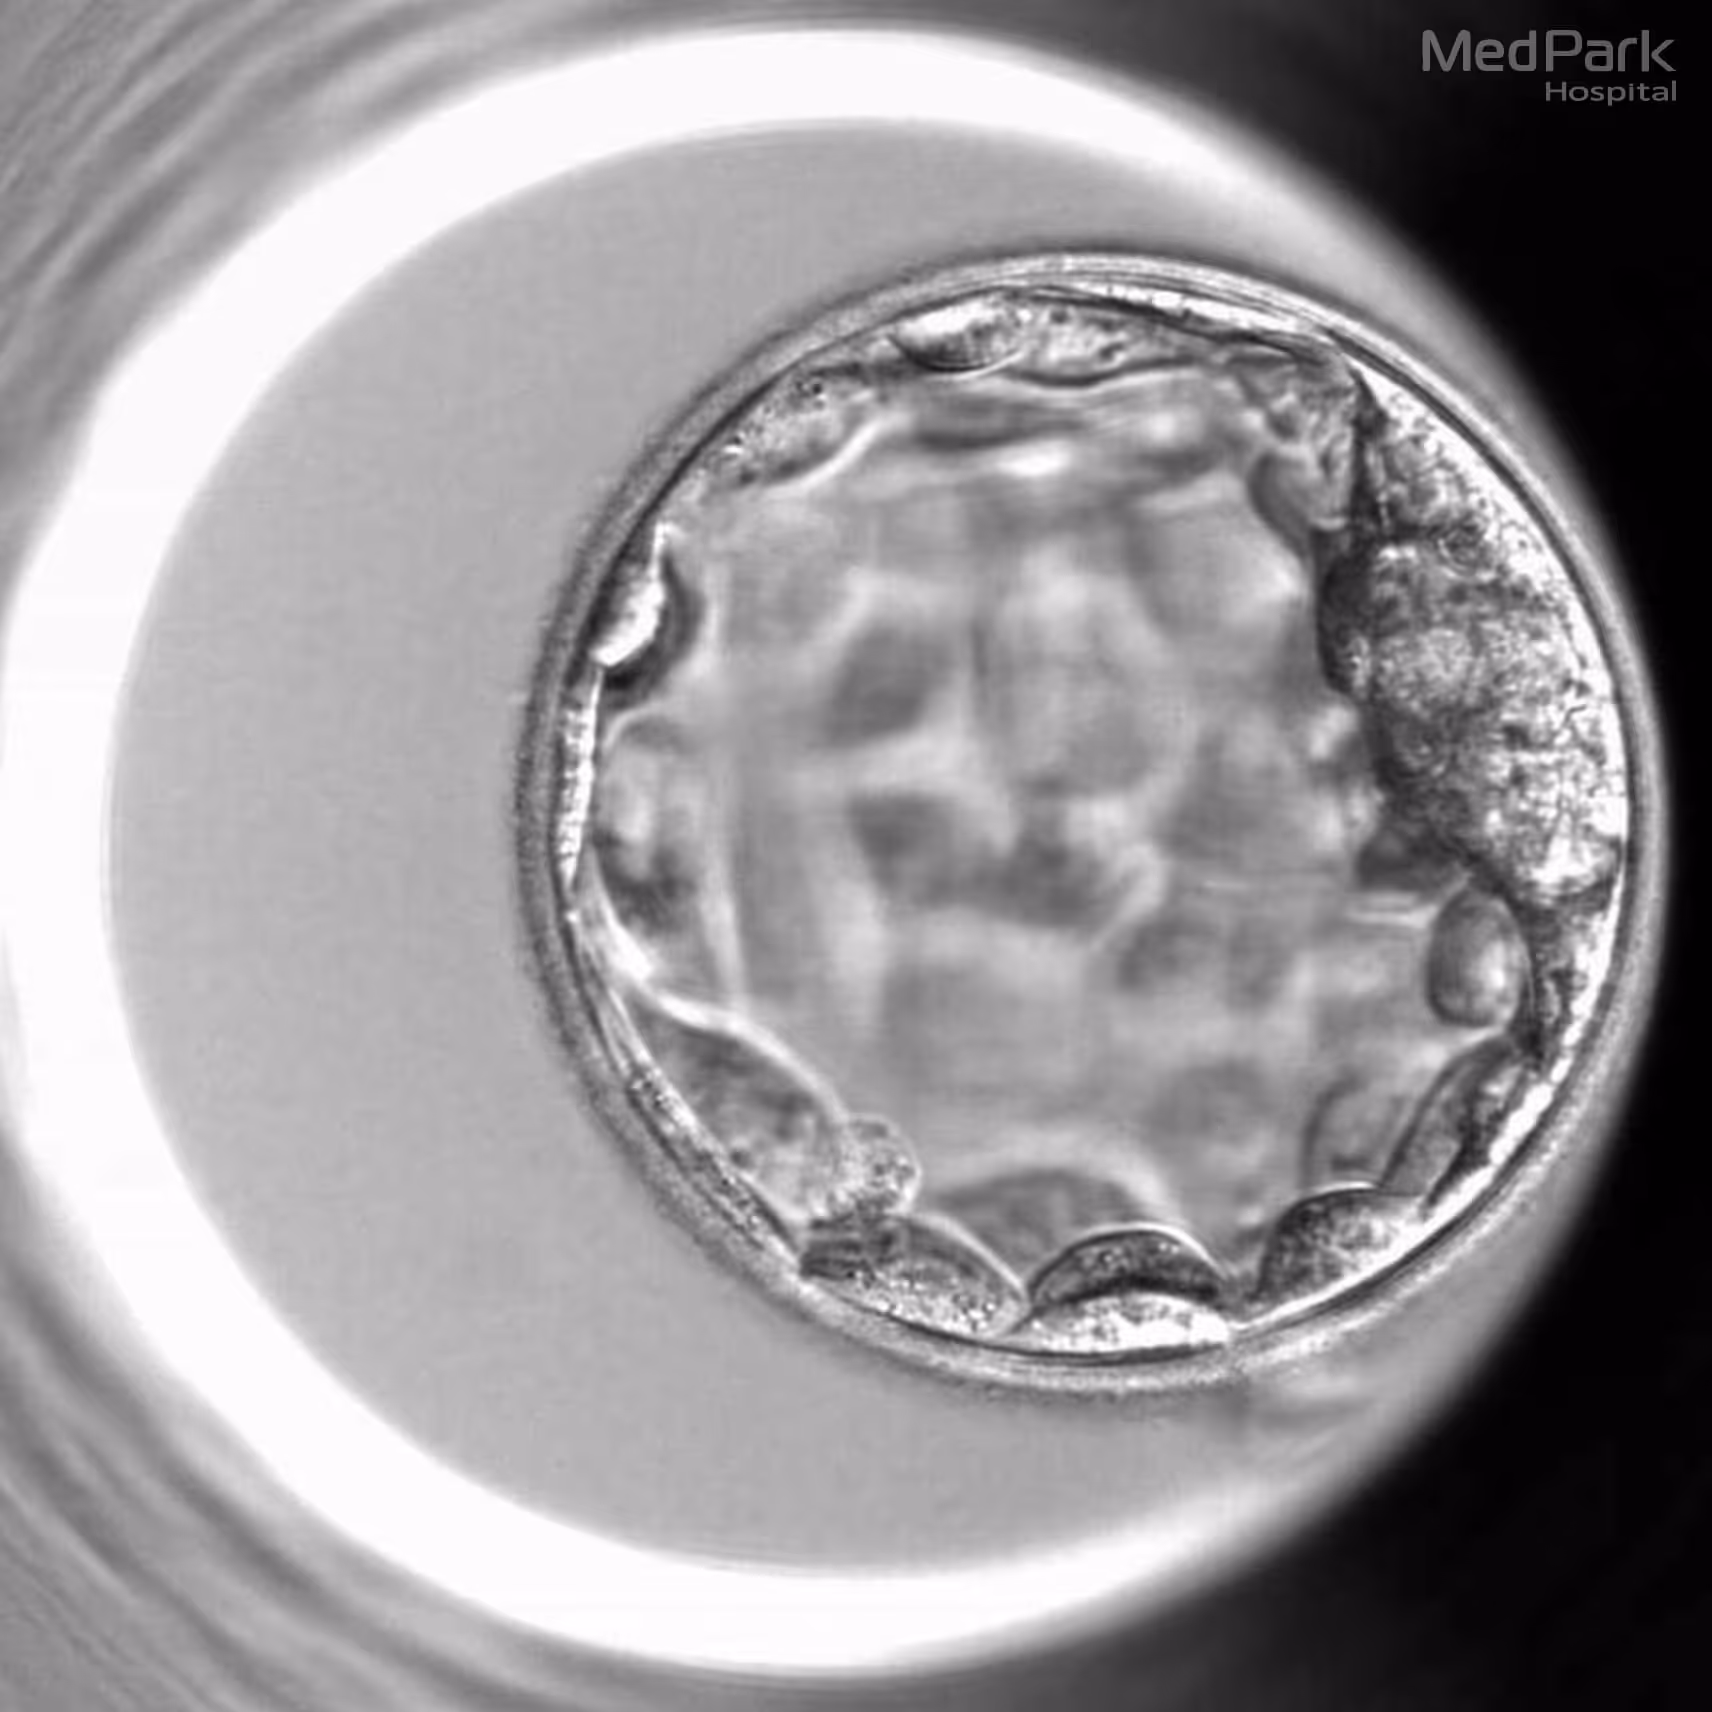

Day-5 Embryo or Blastocyst

At this stage, the inner cell mass (ICM), which will develop into the fetus, and the trophectoderm epithelium (TE), which will become the placenta and other tissues necessary for pregnancy, are formed. The zona pellucida (ZP), the outer protective shell, is ready to break open for the step of implantation in the uterus. The grading system for Day 5 Embryos depends on blastocyst expansion, inner cell mass, and trophectoderm epithelium quality.

• Blastocyst Stage of Expansion

The blastocoel, the fluid-filled cavity within the developing embryo, will be assessed and graded as a number ranging from 1 to 6, with 6 indicating the most advanced expansion.

Grade 1: Early blastocyst - The volume of blastocoel is less than half of the embryo.

Grade 2: Blastocyst – The volume of blastocoel is more than half of the embryo.

Grade 3: Full Blastocyst – The blastocoel fills the embryo.

Grade 4: Expanded Blastocyst – The blastocoel is larger than the embryo. ZP is thinning.

Grade 5: Hatching Blastocyst – TE is bursting through the ZP.

Grade 6: Hatched Blastocyst – TE completely burst through the ZP.

A day-5 embryo with a 5AA grading indicates that the TE of a blastocyst is bursting through the ZP and tightly packed cells of ICM and TE, suggesting a highly favorable embryo for successful implantation and further development.